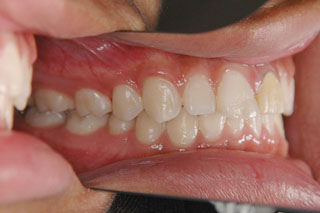

2年半ほどの治療で、装置を撤去し保定治療に移行しています。飛び出ていた前歯も、下の歯と正しく噛めるようになりました。口元の突出も消え、口唇閉鎖時に前歯が覗いて見えるという事も無くなりました。

保定治療に移行してから3年半が経過しました。上の顎に生えてきた親不知は下の顎の奥歯と噛み合うようになりましたが、下の親不知は、斜めに埋まっていましたので、噛み合わせへの変化を防止するためにも早めに抜いて貰いました。矯正治療ではなるべく長期に渡って、管理を行いますが、2年3年と大きな変化が無く、緊密な噛み合わせが確保出来ていれば、将来的にも安定が期待出来ると思います。